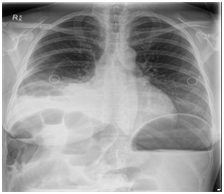

Case patient developed two episodes of large (200ml) green vomit 24hours after the caesarean section. On review, her epigastria pain improved after the delivery but nausea remained. The vomit was brought on by food. Bowel sound was absent on abdominal examination. The abdomen was generally soft and appropriately tender to what one would expect soon after a caesarean operation. A plain abdominal radiograph (AXR) revealed dilated loops of small bowel indicating post-operative ileus. Input from the general surgeons was sought on day two post-op which recommended nasogastric tube (NGT) decompression with free drainage. Chest radiograph (CXR) was ordered to confirm correct position of the NGT. Interestingly, the NGT still remained coiled in the oesophagus on the second CXR see Figure 1 after being repositioned. Despite of this, the NGT was draining stomach content freely and a decision was made not to subject the functional NGT from further repositioning. Case patient’s symptoms did not improve after 24 hours of drainage, therefore a repeat AXR with gastrograffin study see Figure 2 was organised which suggested the possibility of a small bowel obstruction. An abdominal computed tomography (CT) was arranged to confirm and locate the small bowel obstruction. It showed the presence of abdominal content in the right sided chest through a diaphragmatic defect see Figure 3. A right sided non-strangulated diagrammatic hernia was diagnosed. The general surgeons performed an emergency laparoscopic right sided diaphragmatic hernia repair and returned the incarcerated bowel to the abdomen. Upon direct visualisation, 20cm of terminal ileum was herniated through a 6cm defect on the right diaphragm. The defect was approximated and sutured with four interrupted size 0 monofilament nylon sutures. The case patient recovered well after the operation and was discharged home 5 days after with a healthy baby girl.

Figure 2 AXR with Gastrograffin study - The stomach which is significantly distended. Small amounts of ingested contrast are seen in proximal small bowel loops. No contrast is seen in the colon. The features suggest a mechanical mid to distal small bowel obstruction.